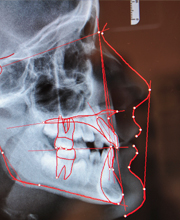

Health and Success − Aesthetics and Function